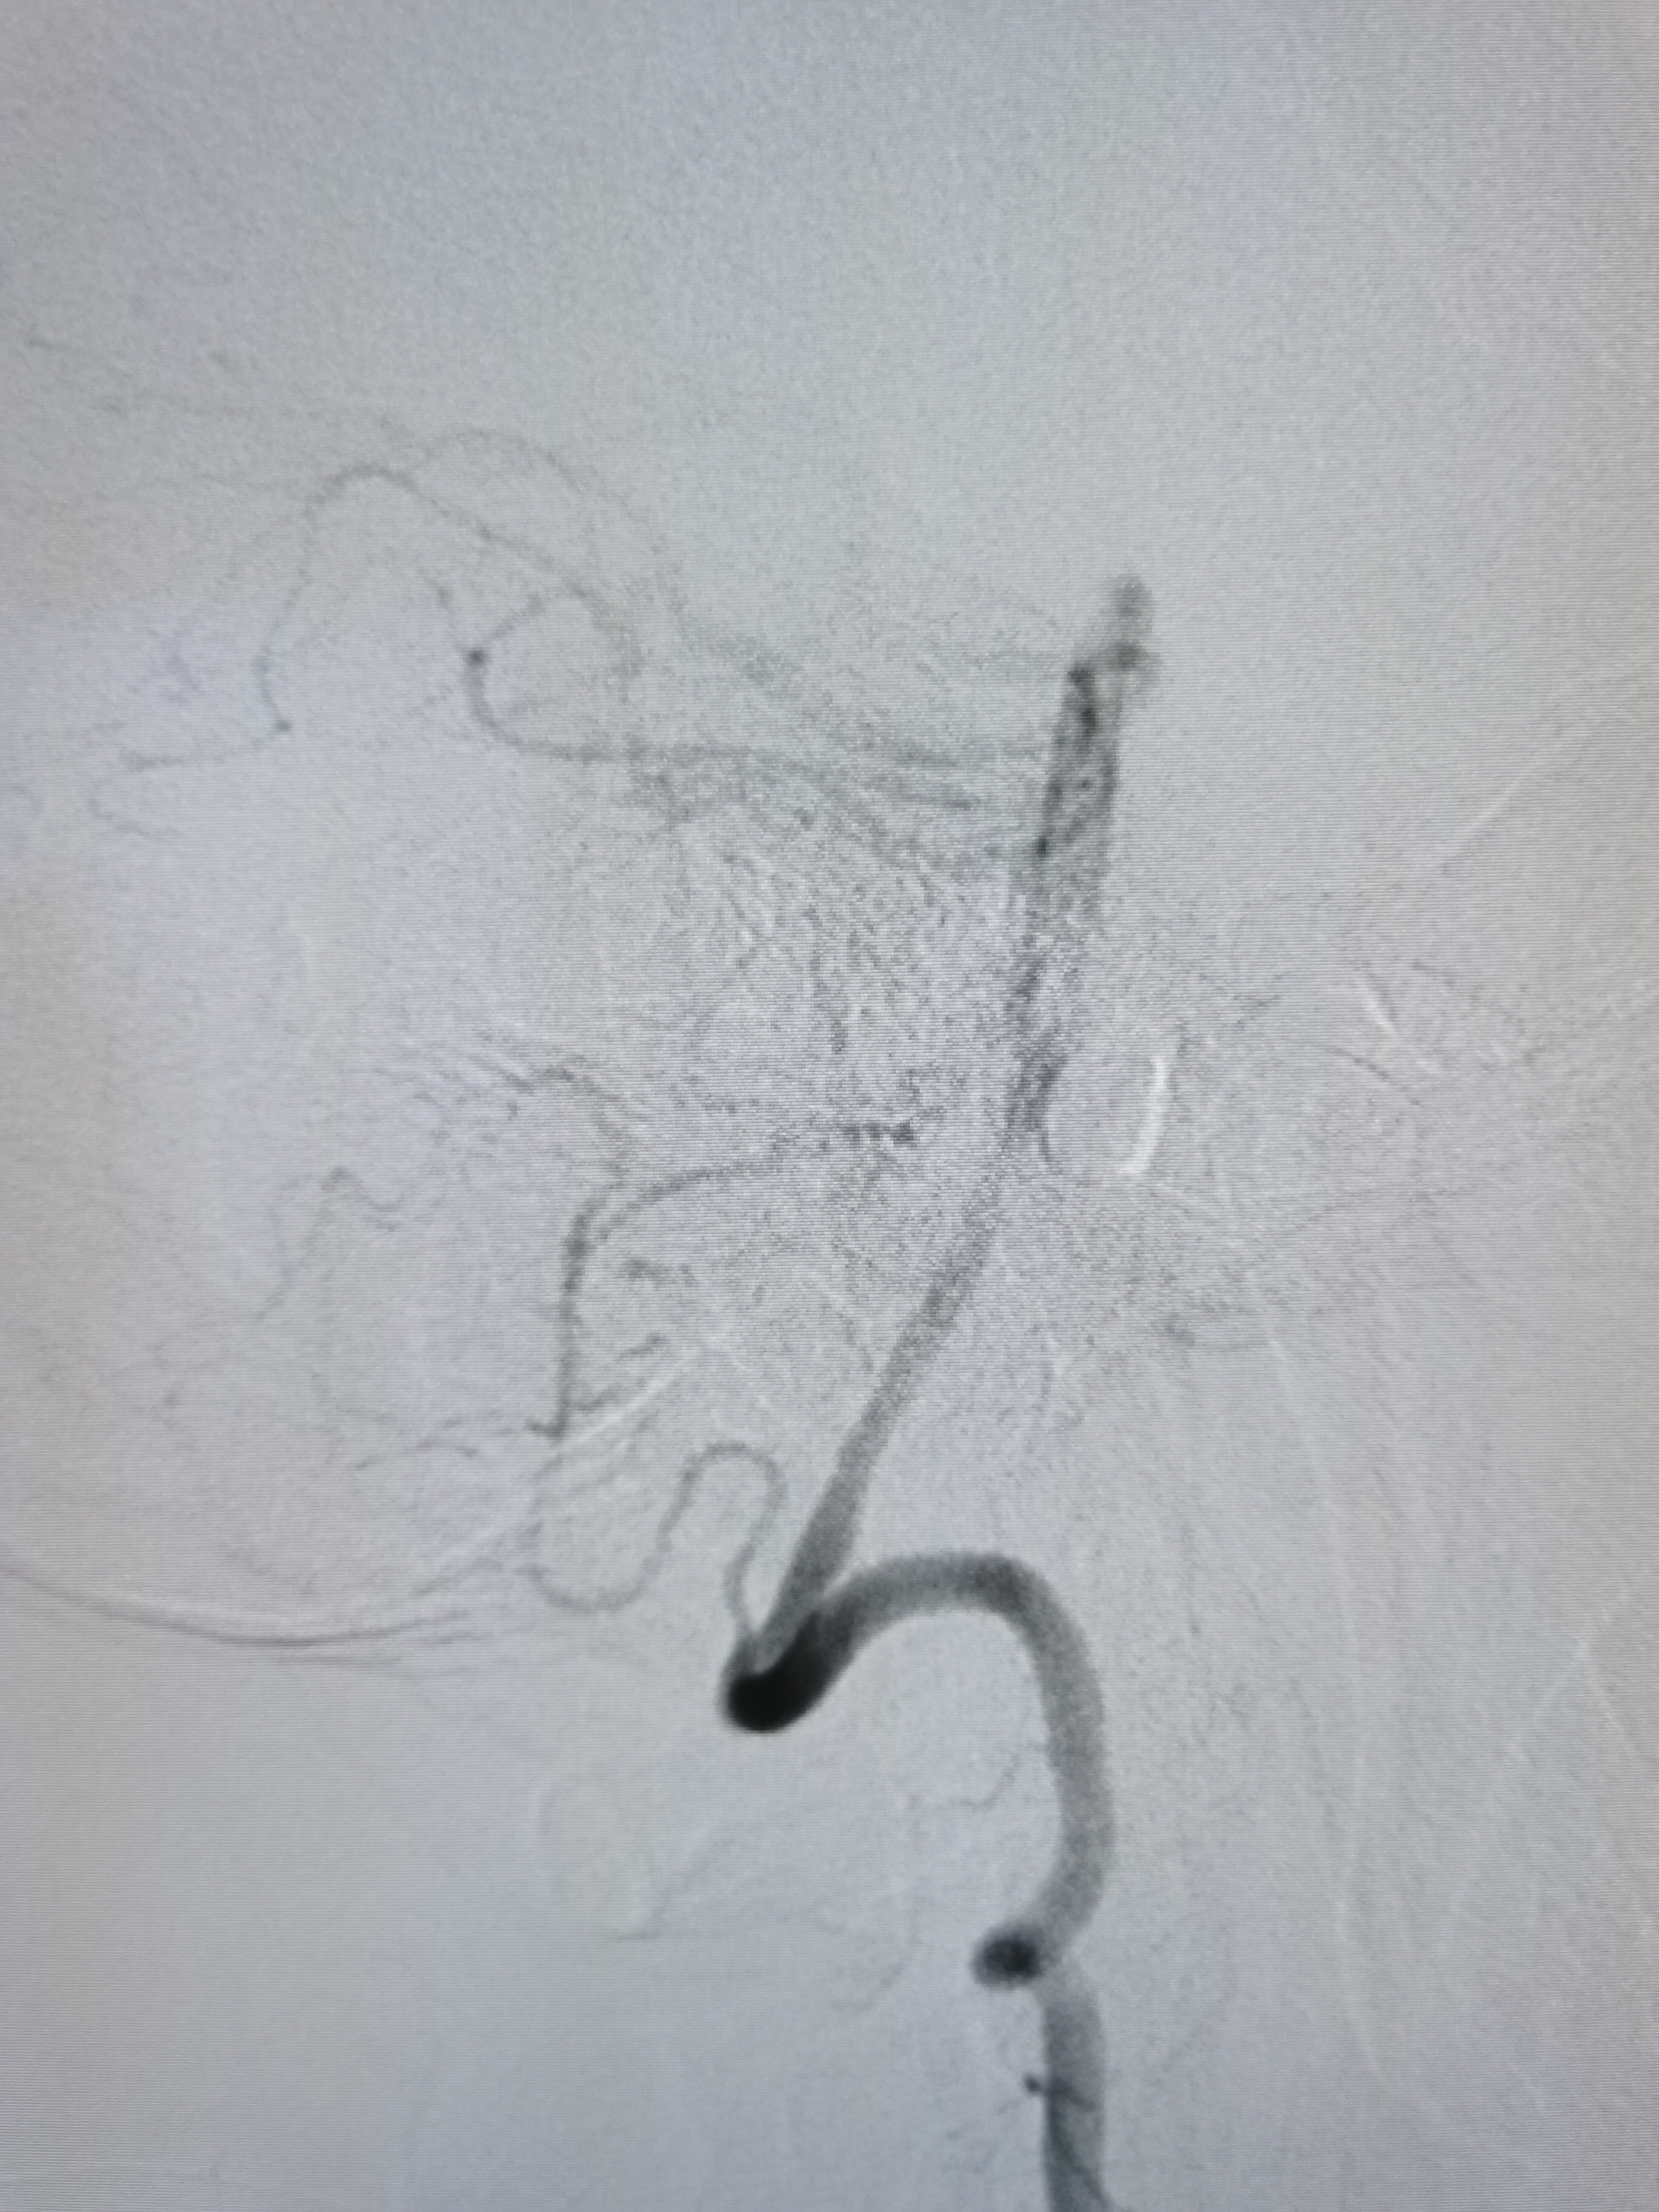

左侧颈内动脉狭窄伴溃疡形成。

颅内段显影可。

双侧大脑前动脉共干。

支架释放后狭窄改善,覆盖不稳定斑块。

支架释放后颅内血供良好。

颅内血供良好。